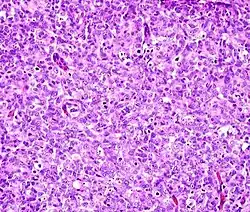

Solid: More or less the same cell type throughout, with no spaces between, and no other particular pattern. -